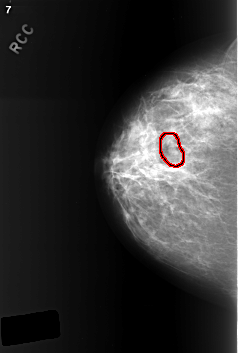

C_0402_1.RIGHT_CC

RIGHT_CC LINES 5640 PIXELS_PER_LINE 3800 BITS_PER_PIXEL 12 RESOLUTION 50 OVERLAY

FILE: C_0402_1.RIGHT_CC.OVERLAY

TOTAL_ABNORMALITIES 1

ABNORMALITY 1

LESION_TYPE MASS SHAPE LOBULATED MARGINS CIRCUMSCRIBED

ASSESSMENT 3

SUBTLETY 4

PATHOLOGY BENIGN

TOTAL_OUTLINES 1

BOUNDARY